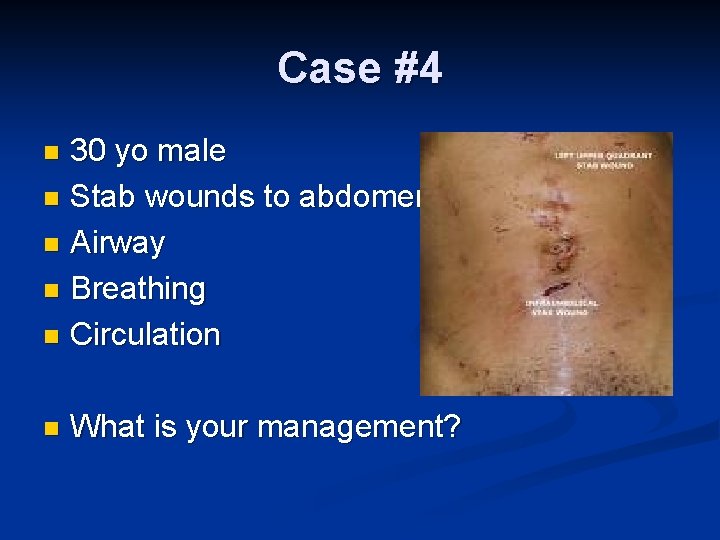

Case #4 30 yo male n Stab wounds to abdomen n Airway n Breathing n Circulation n n What is your management?

Options for Management Diffuse Abdominal Tenderness Yes Laparotomy No Hemodynamic Stability? Indications for Laparotomy – Penetrating Trauma ● ● ● Hemodynamically abnormal Peritonitis Evisceration Positive DPL, FAST, or CT Violation of peritoneum

Options for Management n Hemodynamically stable penetrating injury Serial Observation Wound Exploration DPL CT scan +/- Contrast Laparoscopy Laparotomy Ultrasound/echo – cardiac box Pericardial window – cardiac box